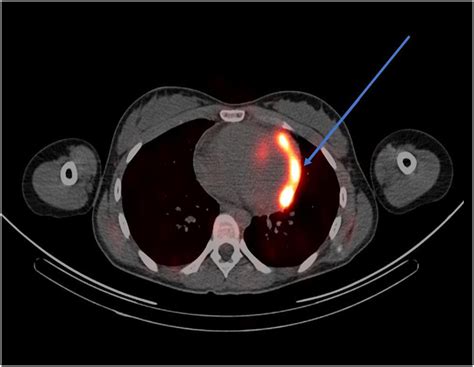

それによると、16-17歳の男児では、ファイザーの遺伝子ワクチンによって、当初の米国疾病予防管理センター(CDC)の発表の3倍も心筋炎が発生していることが報告されました。

遺伝子ワクチンによる子供の心筋炎では、ほぼ100%近くが入院しています(Myopericarditis following COVID-19 vaccination: Updates from the Vaccine Adverse Event Reporting System (VAERS).

今回、12-17歳の子供の新型コロナ感染による入院率と遺伝子ワクチンによる心筋炎の発症率(ほぼ100%入院となる)を比較検討した観察研究が報告されています(SARS-CoV-2 mRNA Vaccination-Associated Myocarditis in Children. Ages 12-17: A Stratified National Database Analysis. medRxiv preprint doi: https://doi.org/10.1101/2021.08.30.21262866)。

12-15歳の男児では、遺伝子ワクチン後の心筋炎の発症率は、新型コロナ感染による入院率の3.7~6.1倍でした。もっとも入院率が高かった2021年1月の時期と比較しても2.6~4.3倍でした。

16-17歳の男児では、遺伝子ワクチン後の心筋炎の発症率は、新型コロナ感染による入院率の2.1~3.5倍でした。もっとも入院率が高かった2021年1月の時期と比較しても1.5~2.5倍でした。

つまり、心筋炎という遺伝子ワクチンのたった一つの有害事象を取り上げただけでも、新型コロナ感染関連入院率より数倍高いという結果が出ているのです。

しかも心筋炎は入院治療で軽快していると政府当局やマスコミは喧伝していますが、その長期的影響はまだ誰も分かりません。